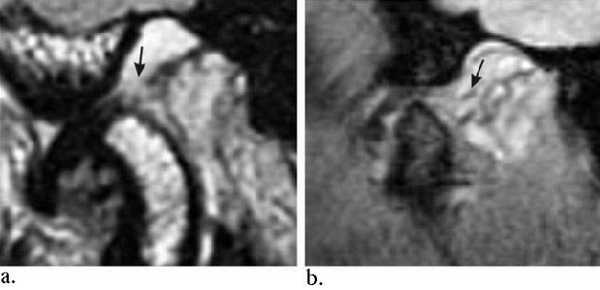

Перемежающийся (вправляемый) вывих /подвывих.

А. Закрытый рот. Переднее смещение диска.

Б. Рот открыт. Диск вернулся в нормальное положение между мыщелком и височной костью.

Фиксированный (невправляемый) вывих.

А. Рот закрыт. Переднее смещение диска.

Б. Рот открыт. Диск продолжает оставаться смещенным.

«Застрявший» диск.

«Застрявший» диск. PD sag изображения с открытым (А) и закрытым (Б) ртом - задний край диска (стрелка) остается в нижнечелюстной ямке височной кости. По этой причине открывание рта сильно ограничено. Вероятная причина - образование спаек.

Заднее смещение диска.

Заднее смещение диска (составляет менее 0,01% всех патологий ВНЧС).

А. Положение с закрытым ртом. Суставной диск сместился дорзально.

Б.Положение с открытым ртом. Возвращение суставного диска на уровень мыщелка нижней челюсти. Движения челюсти очень ограничены в данном случае.